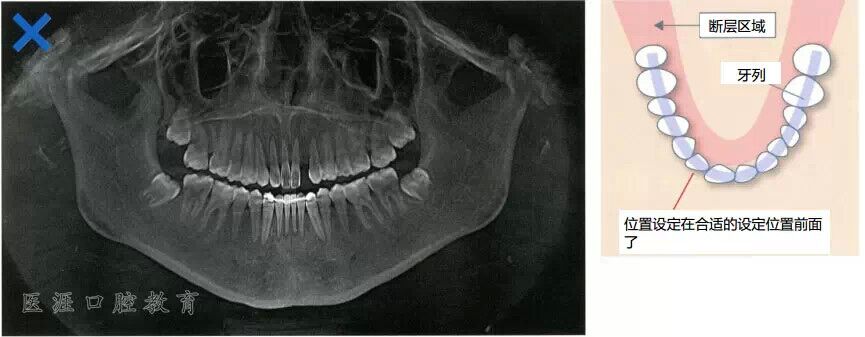

牙列往后方與斷層區(qū)錯(cuò)開